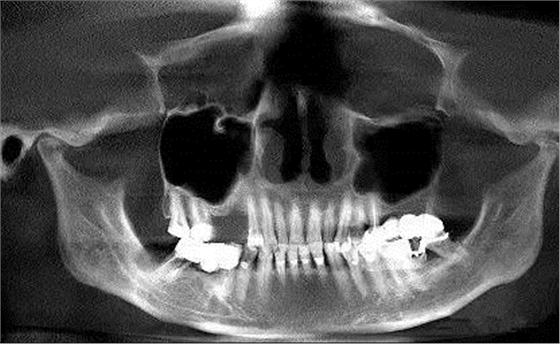

第十圖:上頜竇囊腫,提升區(qū)正好有囊腫,如囊腫小可不處理,直接提升或者抽出囊液減小體積后提升。如果較大,可先將囊腫摘除,三個月后提升(本例采用的就是保留囊腫的外提升已經(jīng)完成兩年)